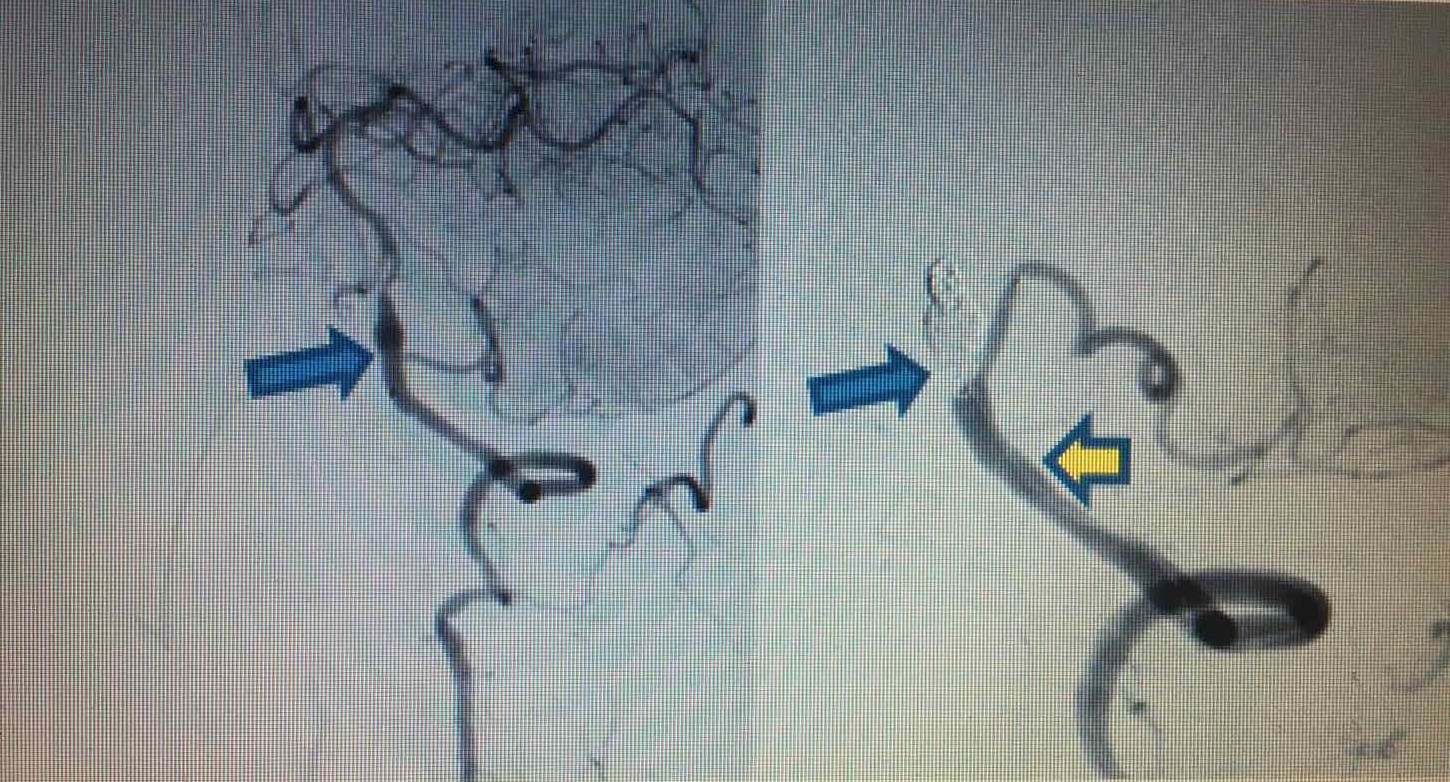

Hình ảnh trước và sau can thiệp (trái: Phình hình thoi bóc tách động mạch) và (phải: Đặt stent động mạch đốt sống - PICA trái và bít coils tắc hoàn toàn phình hình thoi)

Chiều 4/4/2020, ông Tr. Q. T. (57 tuổi, ở Hà Nội) phải nhập viện do đột quỵ não tái phát. Kết quả chụp CT mạch máu não cho thấy ông T. bị phình hình thoi do bóc tách động mạch đốt sống trái lan vào gốc PICA trái. Kíp can thiệp bệnh viện Vinmec Times City đã tiến hành can thiệp đặt stent loại bỏ phình mạch não.

Trước đó, lần đột quỵ đầu tiên của ông T. xảy ra vào chiều ngày 20/3/2020 và đã được cấp cứu kịp thời tại BV Vinmec Times City với chẩn đoán tắc hoàn toàn động mạch đốt sống trái, tắc gốc PICA cùng bên gây nhồi máu cấp tính thùy nhộng và bán cầu tiểu não trái. Lúc đó, người bệnh đã được các bác sĩ chỉ định lấy huyết khối cơ học động mạch não DSA ở giờ thứ 3. “Ưu tiên trong lúc đó là giải quyết phần “ngọn” để cứu tính mạng người bệnh, bởi thời gian can thiệp quá dài có thể quá sức chịu đựng của người bệnh trong bối cảnh đó. Do đó, trong hơn 1h đồng hồ, kíp can thiệp đã tiến hành hút huyết khối, nong bóng qua chỗ hẹp bóc tách và gốc PICA trái để khơi thông được mạch đang bị tắc nghẽn” - ThS.BS Vũ Huy Hoàng, Khoa Chẩn đoán hình ảnh, Bệnh viện Vinmec Times City, người trực tiếp can thiệp cho ông T. chia sẻ.

Tuy nhiên, nguyên nhân đột quỵ não do bóc tách động mạch đốt sống trái vẫn còn nên người bệnh tiếp tục được các bác sĩ khuyến cáo cần theo dõi, chờ can thiệp lần thứ 2.

Do đã rất hài lòng với kết quả can thiệp lần đầu nên ông T. quyết định chưa điều trị ngay lần 2, mặc dù các bác sĩ Vinmec đã hẹn tái khám và tư vấn cần sớm thực hiện can thiệp để loại bỏ gốc rễ gây đột quỵ. Không ngoài dự đoán, ông T. đã bị đột quỵ lại lần 2 chỉ sau chưa đầy 2 tuần. Do đã chẩn đoán chính xác nguyên nhân và có sự chuẩn bị trước nên các bác sĩ Vinmec nhanh chóng can thiệp tối ưu nhất đem lại kết quả phục hồi ngoạn mục cho bệnh nhân.